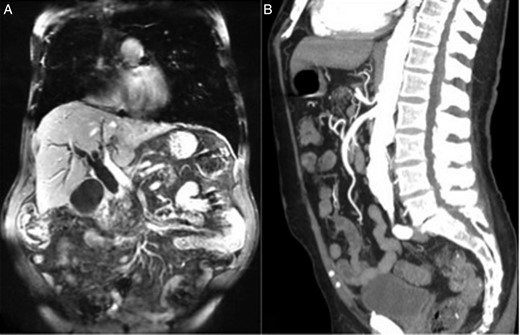

An 83-year-old male patient presented with a chief complaint of painless jaundice. His medical history was significant for lung cancer, bladder cancer, coronary artery disease and history of femoral popliteal bypass surgery for severe peripheral vascular disease. On initial presentation, the patient was afebrile, normotensive and in sinus rhythm. He exhibited no tenderness on abdominal examination. The biochemical studies were significant for a total bilirubin of 5.3 mg/dl, a direct bilirubin of 4.5 mg/dl and an alkaline phosphatase of 561 U/l. Abdominal ultrasound showed a 17-mm common bile duct (CBD) dilatation and moderate intrahepatic ductal dilatation. Magnetic resonance imaging showed a high-grade stricture of the distal CBD, resulting in markedly dilated intrahepatic bile ducts, with 2.6 cm by 1.9 cm soft-tissue fullness at the level of the pancreatic head (Fig. 1A). Abdominal angiography showed moderate narrowing at the origin of the celiac artery; however, the distal celiac, superior mesenteric and inferior mesenteric arteries were patent (Fig. 1B). Positron emission tomography–computed tomography showed no recurrent disease of lung and bladder cancer and no significantly abnormal uptake within the pancreatic lesion. Endoscopic retrograde cholangiopancreatography was performed with sphincterotomy, CBD dilatation and concurrent placement of a 7-cm, 10-Fr stent.

(A) MRI of the abdomen demonstrated marked intrahepatic biliary dilatation due to an abrupt high-grade stricture of the distal CBD at the level of the pancreatic head. (B) CT angiography of the abdomen showed patent celiac artery despite moderate narrowing at the origin of the celiac artery.